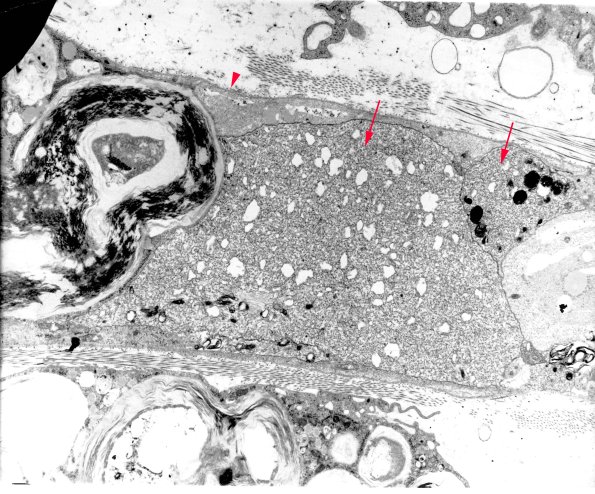

In freely regenerating nerves, growth cones (arrows) can have a distinctive but unimpressive appearance, In 1A6 the original surface of the Schwann cell (arrowhead) constrains the regenerating fibers. (electron micrographs)